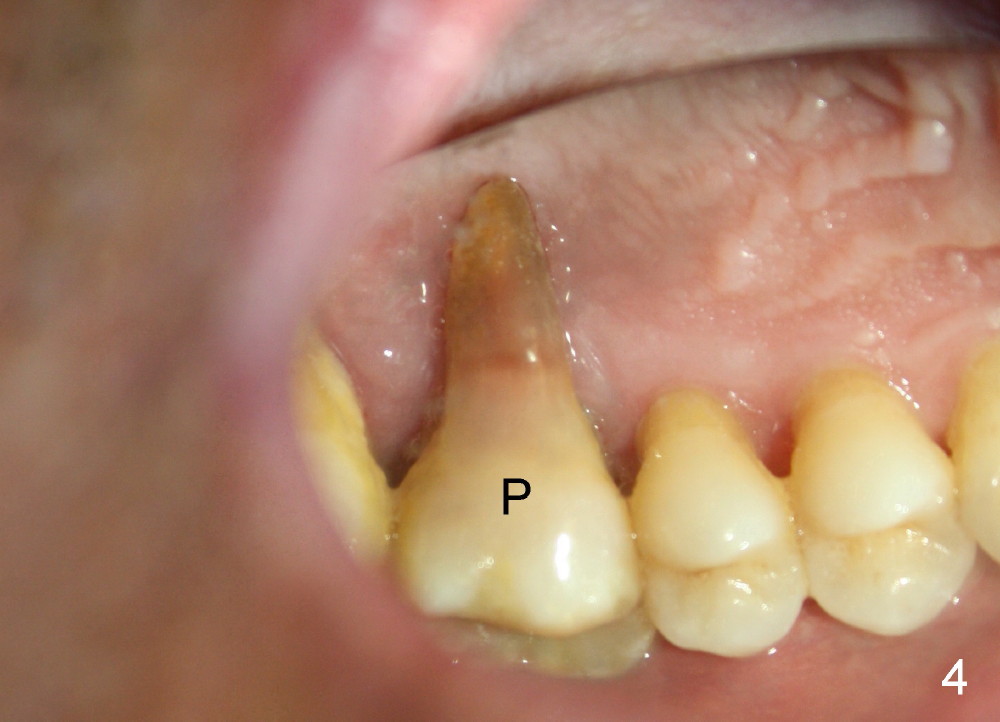

The upper right 1st molar of a 48-year-old man has severe perio endo disease (Fig.1 #3); the bone height for immediate implant (Fig.2) is about 3.5 mm (Fig.1 vertical line). There is a buccal (Fig.3 B) abscess (*); the palatal (Fig.4 P) root is exposed. After extraction, the socket available for immediate implant (Fig.5,6 S) is buccal (without septum), whereas the apex of the palatal root is far away from the main socket. In fact there is an advantage: the socket is smaller. Osteotomy is created in the main socket as palatal as possible, using osteotomes, reamers and taps (Fig.7 T). The sinus floor is lifted (Fig.7 ^). When 7x17 mm implant is placed (Fig.8 I), the insertion torque is >60 Ncm. The remaining socket (Fig.8 *) is to be packed with mixture of autogenous bone, allograft and synthetic bone (Osteogen) (Fig.9,10 <). Immediate insertion of an abutment (Fig.8-10 A) helps retain perio dressing (Fig.11,12). No collagen membrane is used in this case to cover the bone graft before placement of perio dressing. Postop the patient cannot tolerate oral Amoxicillin because of stomach upset. The dose is reduced. Two weeks postop, the perio dressing is stable, but discolors (Fig.13). When the dressing is removed, the buccal bone graft is exposed, which is not abnormal. What is unusual is discoloration (Fig.14). The significance of the latter is not revealed until 3 months postop when the patient remains asymptomatic, but there is an apical fistula (Fig.15 <). There is a communication between the fistula and the buccal sulcus of the implant: water passing freely. Based on the position of the buccal plate of the neighboring teeth (*), the buccal plate of the implant should be lost, which is consistent with finding of PA (Fig.16, as compared to Fig.8). Guided bone regeneration seems necessary.